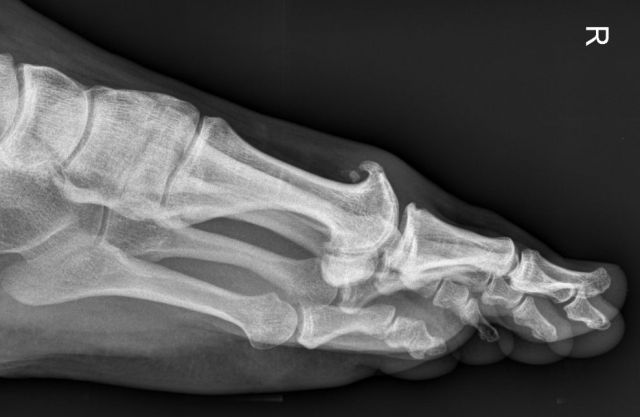

Am Großzehengrundgelenk treten häufig Abnützungsveränderungen (Arthrose) auf. Dabei werden vor allem „oben" am Gelenk knöcherne Anlagerungen tastbar. Diese führen einerseits zu Schmerzen, andererseits zu einer Bewegungseinschränkung des Großzehens.

Ursächlich ist häufig eine traumatische Vorgeschichte, eine Hallux valgus Deformität oder eine familiäre Belastung.